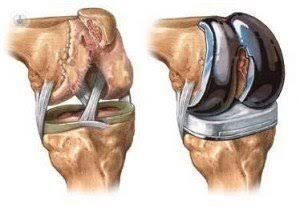

La Prótesis de rodilla, también llamada artroplastia de rodilla o reemplazo total de rodilla, es un procedimiento quirúrgico para reconstruir una rodilla dañada por la artritis, o lesiones severas. Se utilizan piezas de metal y plástico para cubrir los extremos de los huesos que forman la articulación de la rodilla, junto con la rótula. Esta cirugía puede considerarse para alguien que tenga artritis grave o una lesión grave de rodilla.

El objetivo de la cirugía de prótesis de rodilla es reconstruir las partes de la articulación de la rodilla que se han dañado y aliviar el dolor de rodilla que no se puede controlar con otros tratamientos.